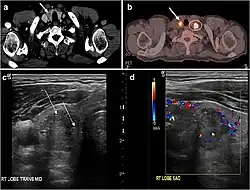

![Fig. 9. A 58-year-old male patient with persistence PTC at thyroid bed with hypervascular nodal metastasis. a–c Transverse greyscale and colour Doppler neck ultrasound demonstrate hypoehoic soft tissue in the left thyroid bed (white arrow in a). There are a heterogeneous enlarged lymph nodes at level 2 and 3 with markedly increased vascularity (white arrow in b and c). d–f Enhanced axial CT images of the neck demonstrate a 2.7 × 1.4 cm hypodense soft tissue lesion anterior to the left carotid sheath (white arrow). There are left-sided enhancing abnormal and enlarged lymph nodes at cervical level 2 and 3 (black arrows).[1]](./_assets_/Ultrasonography_and_CT_of_persistent_papillary_thyroid_carcinoma_with_nodal_metastasis.jpg) Fig. 9. A 58-year-old male patient with persistence PTC at thyroid bed with hypervascular nodal metastasis. a–c Transverse greyscale and colour Doppler neck ultrasound demonstrate hypoehoic soft tissue in the left thyroid bed (white arrow in a). There are a heterogeneous enlarged lymph nodes at level 2 and 3 with markedly increased vascularity (white arrow in b and c). d–f Enhanced axial CT images of the neck demonstrate a 2.7 × 1.4 cm hypodense soft tissue lesion anterior to the left carotid sheath (white arrow). There are left-sided enhancing abnormal and enlarged lymph nodes at cervical level 2 and 3 (black arrows).[1]

Fig. 9. A 58-year-old male patient with persistence PTC at thyroid bed with hypervascular nodal metastasis. a–c Transverse greyscale and colour Doppler neck ultrasound demonstrate hypoehoic soft tissue in the left thyroid bed (white arrow in a). There are a heterogeneous enlarged lymph nodes at level 2 and 3 with markedly increased vascularity (white arrow in b and c). d–f Enhanced axial CT images of the neck demonstrate a 2.7 × 1.4 cm hypodense soft tissue lesion anterior to the left carotid sheath (white arrow). There are left-sided enhancing abnormal and enlarged lymph nodes at cervical level 2 and 3 (black arrows).[1]